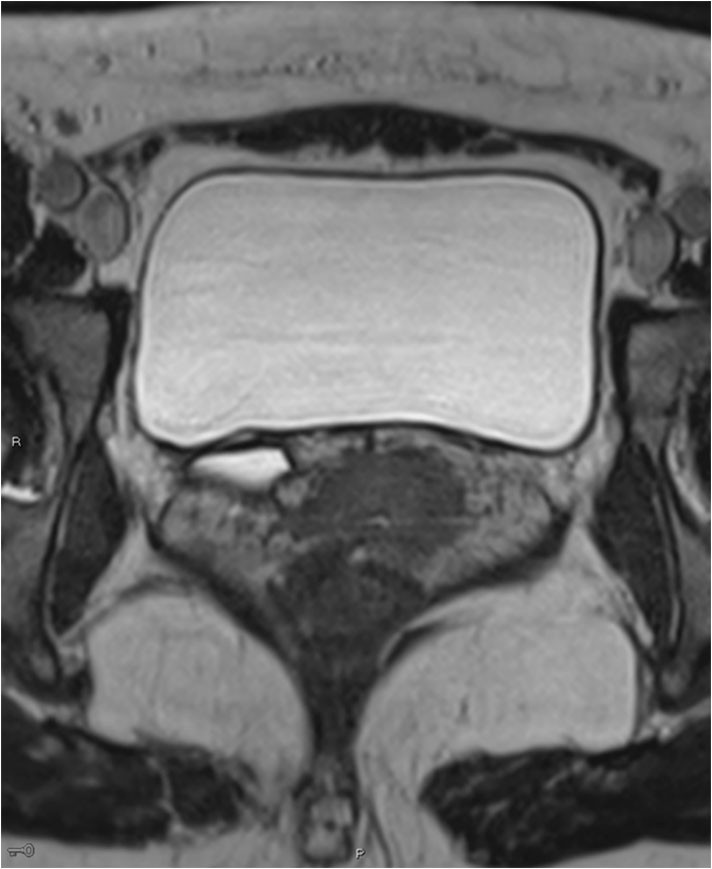

A CT scan of the urinary tract was performed, but proved inconclusive with respect to ureteral ectopia. MRI of the urinary tract was therefore performed in addition. This revealed a right-sided duplex collecting system with a small upper collecting system and a dilated ureter (Figure 1). The ureter was dilated from the bladder to the vagina and opened out ectopically near the urethral opening (Figure 2).

Figure 2 MRI. Transverse 3D section with high resolution T2 weighting shows a right-sided dilated ectopic ureter.

Identification of a duplex collecting system and ectopic ureter on CT requires adequate function and contrast excretion from the upper collecting system, which was not the case in this patient. It is possible to detect a dilated ectopic ureter with ultrasound, but this can be difficult unless the condition is specifically looked for. Our patient was referred with suspected cholelithiasis and pyelonephritis, and no pathology was detected upon routine examination of the urinary tract. High-resolution fluid-sensitive volumetric MRI sequences are good for identifying the ureter and tracing its course. MRI is more appropriate than CT in the lesser pelvis, but more time-consuming. Dedicated high-resolution series in the pelvis were supplemented with less detailed sequences of the upper urinary tract. No contrast agent was used during the MRI scan. Paediatricians use MRI as the primary imaging modality upon suspicion of ureteral ectopia.